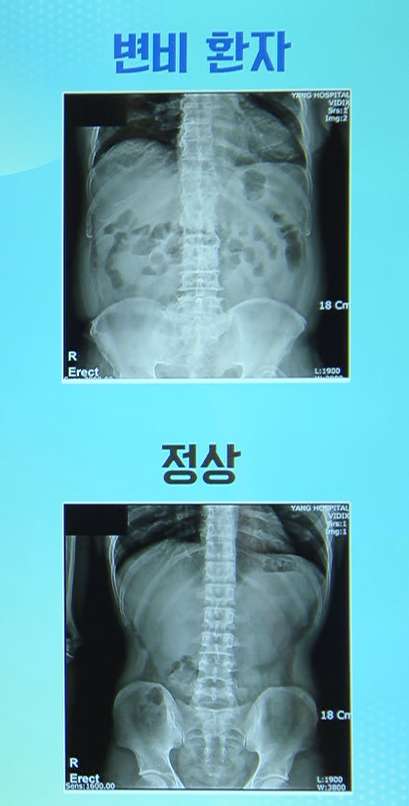

아래 사진을 보시면 밑에가 정상인데 위에 있는 것은 가스가 많이 차 있잖아요. 가스하고 대변이 있는 거예요.

그리고 이렇게 변비가 있으면 우리 몸에서 유해균이 늘고 유익균이 줄어들어요. 거기에다가 변이 딱딱해지잖아요. 그럼 이게 염증들을 키우고 심한 경우는 천공(장에 구멍이 생기는 것)이 됩니다. 그래서 미국에서 1년에 900명이 변비로 죽는다고 합니다. 너무 딱딱해서 장을 막아버리는 거예요.